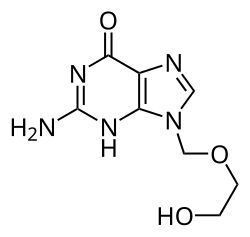

- Вирусы, использующие обратную транскрипцию. Эти вирусы содержат одноцепочечную РНК (Retroviridae, Metaviridae, Pseudoviridae) или двухцепочечную ДНК (Caulimoviridae и Hepadnaviridae). РНК-содержащие вирусы, способные к обратной транскрипции (ретровирусы, например ВИЧ), используют ДНК-копию генома как промежуточную молекулу при репликации, а содержащие ДНК (параретровирусы, например вирус гепатита B) — РНК[116]. В обоих случаях используется обратная транскриптаза, или РНК-зависимая ДНК-полимераза. Ретровирусы встраивают ДНК, образующуюся в процессе обратной транскрипции, в геном хозяина, такое состояние вируса называется провирусом. Параретровирусы же этого не делают, хотя встроенные копии их генома могут давать начало инфекционным вирусам, особенно у растений[117]. Вирусы, использующие обратную транскрипцию, восприимчивы к противовирусным препаратам, ингибирующим обратную транскриптазу, в том числе к зидовудину и ламивудину.

Противовирусные препараты часто представляют собой аналоги нуклеозидов. Они встраиваются в геном вируса в ходе репликации, и на этом жизненный цикл вируса останавливается, поскольку новосинтезированная ДНК неактивна. Это вызвано тем, что у аналогов отсутствуют гидроксильные группы, которые вместе с атомами фосфора соединяются и формируют жёсткий «остов» молекулы ДНК. Это называется цепной терминацией ДНК[209]. Примеры аналогов нуклеозидов — ацикловир, применяющийся против инфекций, вызванных простым вирусом герпеса, и ламивудин (против ВИЧ и вируса гепатита B). Ацикловир — один из старейших и наиболее часто назначаемых противовирусных препаратов[210]. Другие используемые противовирусные препараты имеют мишенью различные стадии жизненного цикла вирусов. Вирусу иммунодефицита человека, чтобы стать полностью заразным, необходим протеолитический фермент, известный как ВИЧ-1 протеаза. На основании этого разработан большой класс препаратов, называемых протеазными ингибиторами, инактивирующими этот фермент.